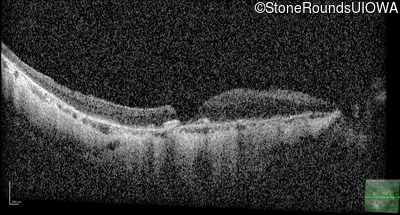

Optical Coherence Tomography - Right - 20/40 -2

Exemplar / OCT Stack